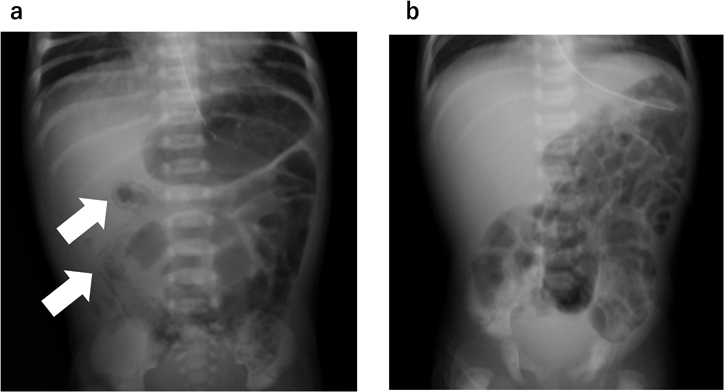

Fig. 1 Abdominal X-ray

(a) Abdominal radiograph obtained at day 8 showed pneumatosis intestinalis at arrows. At 8 days of age. (b) Abdominal radiograph obtained at day 26 showed partial small intestinal gas deficiency area, whereas colon gas was not obscure, suggesting poor small intestinal peristalsis and fluid retention.

日齢1にPDA 4 mmでほぼ左–右短絡となり,SpO2が上下肢ともに94%まで上昇,血圧86/28 mmHgと拡張期血圧の低下を認め,胸部X線にてうっ血所見を呈したため窒素ガス吸入による低酸素換気療法と利尿剤の投与を開始し,PGE1-CDは5 ng/kg/分に減量した.また生後6時間で人工乳による経腸栄養を開始し,日齢4より母乳の併用を行ったが,軽微な症状を含め腹部症状は認めなかった.日齢7に術前評価目的に胸部造影CT検査を施行したところ,日齢8に腹部膨満,血便,血圧低下,およびショック症状を呈した.腹部単純X線像では,小腸の腸管壁内気腫像を認めたが腹腔内に遊離ガス像はみられず(Fig. 1a),血液検査では,白血球数24,500/µL(好酸球数0/µL),CRP 1.07 mg/dLと炎症反応の上昇を認めたため,NEC(Bell分類II期)および敗血症と診断した.経腸栄養を中止し気管内挿管,人工呼吸管理,カテコラミン製剤,抗菌薬(MEPM, VCM, TAZ/PIPC),ガンマグロブリン製剤の投与を行ったところ症状出現から17時間後には血便は消失,腹部単純X線検査の腸管壁内気腫像は改善した.日齢13に抗菌薬を中止し,同日に心臓カテーテル検査による冠動脈走行の診断(Shaher分類4型)を行い,日齢14に大血管スイッチ術を施行した(Fig. 2).

術後の経過は良好で,日齢15(術後1日)に抜管,日齢16にカテコラミン製剤を中止した.便は粘液便であったが血便はなく,日齢20より人工乳による経腸栄養を再開した.その後の便性は水様だが1日2回程度であり,便量や便回数の増加は認めなかったものの,腹部膨満の症状が出現し,胃内残渣が多く経腸栄養を進めることができなかった(Fig. 3).日齢26の腹部単純X線像でも,部分的な小腸ガス欠損域を認め,それに対し結腸ガスが目立たないことから小腸蠕動不良と腸液貯留を示唆する所見と判断した(Fig. 1b).NEC後の消化管狭窄病変の鑑別を行うため,上部消化管造影検査を施行し,胃の蠕動低下を認めたが,造影1時間後,3時間後,8時間後のX線像で小腸・結腸の通過障害は認めず,狭窄性病変もみられなかった.血液検査では,末梢血好酸球数が増多(1,251/µL)を示したことから,新生児・乳児食物蛋白誘発胃腸症を疑い高度加水分解乳(ニューMA-1®:森永乳業)に変更した.同日に提出した非特異的IgE:<3 U/mLと牛乳・α–ラクトアルブミン・β–ラクトグロブリン・カゼインの抗原特異的IgEは低値であったが,アレルゲン特異的リンパ球刺激試験(allergen-specific lymphocyte stimulation test: ALST)ではラクトフェリン:SI(Stimulation Index)=5.07(カットオフ値2.62),β–ラクトグロブリン:SI=3.03(カットオフ値2.10)が高値であった(Table 1).高度加水分解乳に変更後は順調にミルクの増量が可能となり良好な体重増加が得られたため,新生児・乳児食物蛋白誘発胃腸症と診断した.日齢62に退院し現在外来での定期受診を行っているが,消化器症状の再燃はなく経過は良好である.